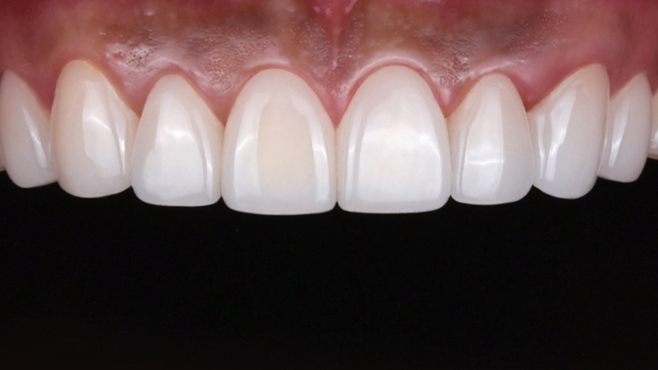

맞는 건 괜찮은데… 충치는 못 참겠습니다|20대 격투기 선수 치과 방문기